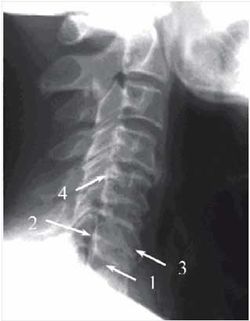

В подавляющем большинстве случаев рентгенологическое исследование, в первую очередь проводящееся для исключения потенциально опасных заболеваний, симптомом которых может быть боль в спине (рис. 8), выявляет также дистрофические изменения позвоночника (остеохондроз) в виде уменьшения межпозвоночных промежутков, субхондрального остеосклероза, формирования остеофитов, кальцификации пульпозного ядра и (или) фиброзного кольца, артроза дугоотростчатых суставов, скошенной формы тел и смещение позвонков (рис. 9). Рентгенография позвоночника помогает в диагностике спондилолистеза (рис. 10), классификация которого основана на степени смещения вышележащего позвонка относительно нижележащего. I степени спондилолистеза соответствует смещение тела позвонка менее чем на 25% его сагиттального размера, II - на 25-50%, III - на 50-75%, IV - на 75-100%. I и II степени относят к умеренно выраженному спондилолистезу.

При рентгенографии с функциональными пробами (сгибание, разгибание в шейном или поясничном отделе позвоночника) возможно выявление ограничения подвижности (функциональной блокады) или гипермобильности (нестабильности) отдельных ПДС (рис. 11).

Строение тел III-VI шейных позвонков отличается тем, что по заднелатеральному их краю формируются так называемые крючки тела позвонка. В норме между ними и телами расположенных выше позвонков находится межпозвоночный диск. При этом крючки тела позвонка препятствуют сдавлению спинномозговых нервов при задней протрузии межпозвоночного диска. Однако по мере уменьшения высоты диска и увеличения размеров крючков они достигают нижней поверхности дуги вышележащего

Отмечается субхондральный остеосклероз (черная пунктирная стрелка), снижение высоты межпозвоночного промежутка (белая пунктирная стрелка), формирование остеофитов (белая стрелка), задний спондилолистез (черная стрелка) позвонка, формируя там неоартроз - унковертебральное сочленение, которое нельзя считать истинным синовиальным сочленением [Д.Г. Боренштейн и др., 2005; П.Л. Жарков, 1994].